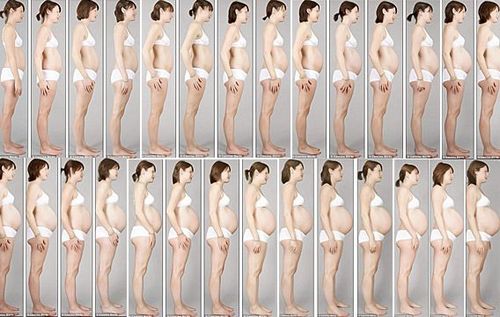

Повні дев'ять місяців вагітності важливі як для мами, так і для дитини. Давайте дізнаємося чому.

Статистика показує, що кількість недоношених малюків (народжених до 37 тижня гестації) зростає з кожним роком: з 1981 року це число виросло на 31%, або один з восьми новонароджених.